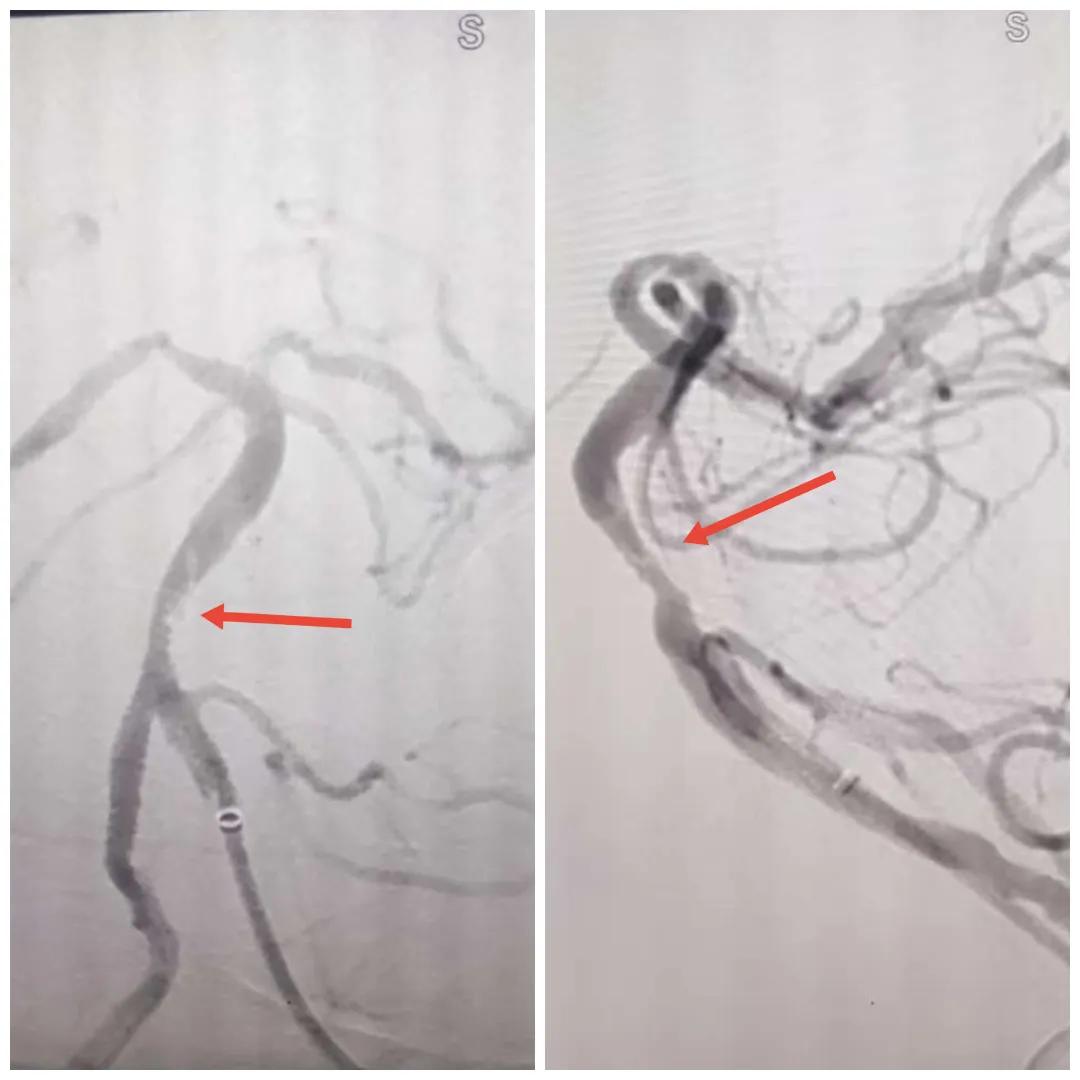

在經(jīng)造影后,主刀醫(yī)生腦一科副主任楊慶堂發(fā)現(xiàn)患者基底動脈下段重度狹窄且狹窄段以遠(yuǎn)有大負(fù)荷血栓,其狹窄處考慮為動脈夾層,手術(shù)難度及風(fēng)險(xiǎn)較大。楊慶堂副主任在彭壯副主任醫(yī)師的協(xié)助下運(yùn)用spaceman(太空人)技術(shù),中間導(dǎo)管抵近血栓抽吸配合支架拉栓,成功開通血管。再次造影可見基底動脈管腔明顯增寬,遠(yuǎn)端血管顯影良好,且等待20分鐘后造影仍顯示血流通暢。楊慶堂副主任考慮到本次手術(shù)時(shí)間不宜過長,現(xiàn)患者基底動脈及分支前向血流維持良好,給予其抗栓藥物應(yīng)用后結(jié)束手術(shù),并建議患者3個(gè)月后復(fù)查造影,明確其基底動脈夾層情況。

取栓后血管管腔增寬,前向血流良好